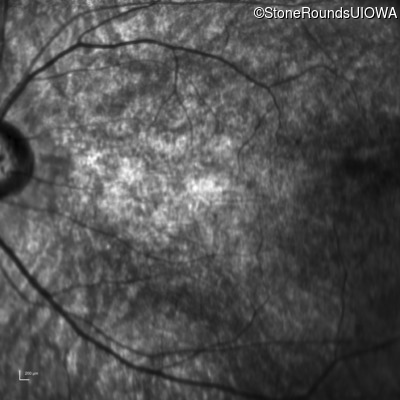

Infrared Fundus Photograph - Left - 20/250

Exemplar